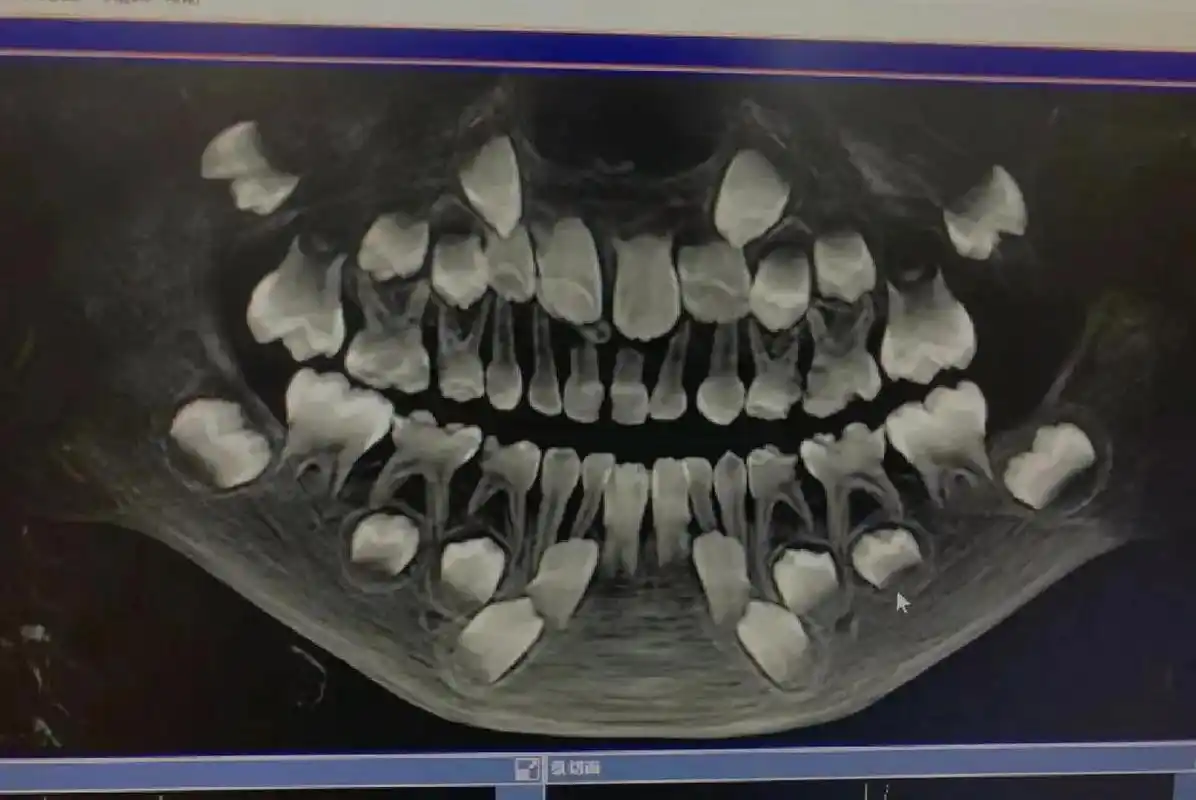

孩子今年7岁,这是在诊所拍的片子,哪位内行人能帮忙看看这个上中切牙

第一次见小朋友的牙片……真是满嘴牙

换牙期小朋友的牙片可以清楚看到有四排牙齿 (还有两颗是长在眼睛下方

替牙期儿童拍摄全景牙片的意义这个孩子发现有多生牙和牙胚缺失

8岁儿童扩弓矫正 图一:牙片 有腺样体肥大,张口呼吸情况,6岁已手术